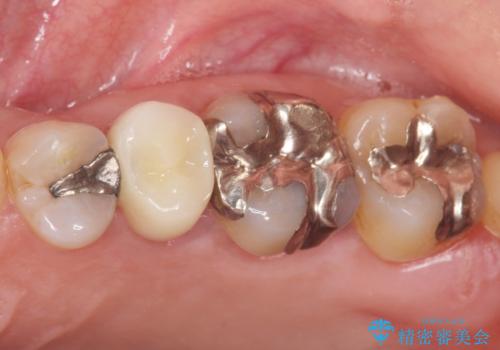

根管治療後、セラミッククラウンによる補綴を行いました。

根管治療により症状がなくなり、またセラミッククラウンの自然な仕上がりにご満足頂けました。

クラウンの種類:オールセラミッククラウン スタンダード